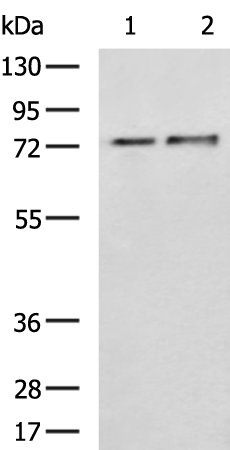

分类: 科研抗体货号: P04874别名: F1AA; F1A-ALPHA; FEM1-beta应用: WB,IHC反应种属: Human, Mouse, Rat